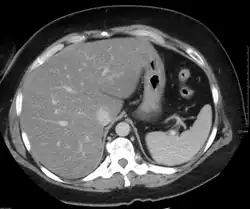

Liver steatosis (fatty liver disease) as seen on CT

On X-ray computed tomography (CT), the increased fat component will decrease the density of the liver tissue, making the image less bright. Typically the density of the spleen and liver are roughly equivalent. In steatosis, there is a difference between the density and brightness of the two organs, with the liver appearing darker.[12] On ultrasound, fat is more echogenic (capable of reflecting sound waves). The combination of liver steatosis being dark on CT and bright on ultrasound is sometimes known as the flip flop sign.